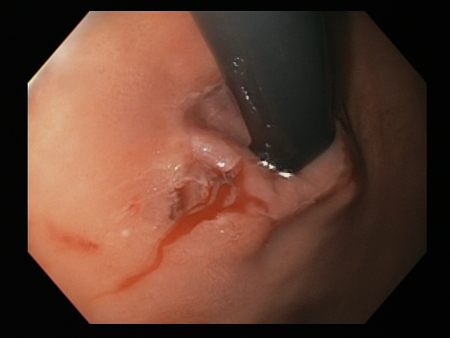

Epinephrine (adrenaline) is injected locally around the site of the Mallory-Weiss tear

From the collection of Juan Carlos Munoz, MD, University of Florida